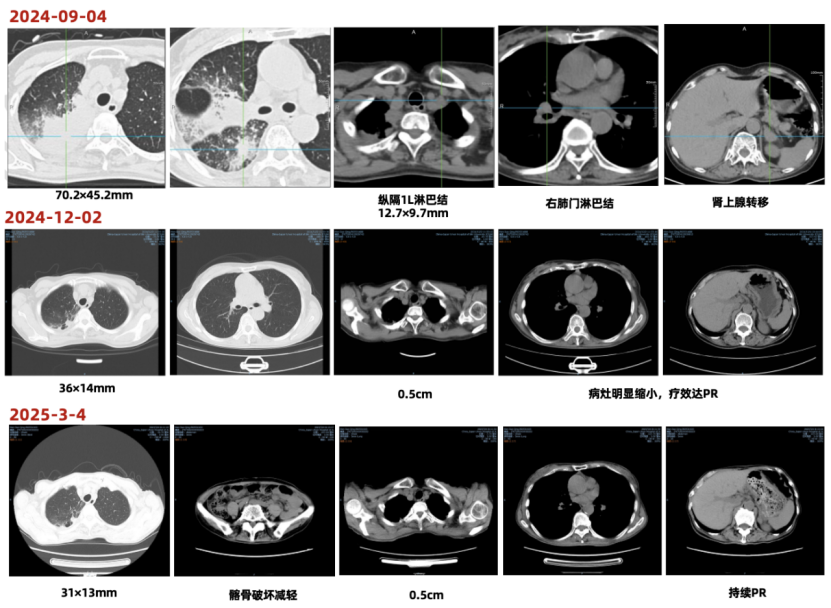

• 2024-09-04 PET-CT:1. 右肺上叶伴糖代谢增高的团片状密度增高影,最大SUV值12.39,最大横截面约70.2×45.2mm,邻近支气管截断,考虑为周围型肺 MT,伴远端阻塞性肺炎;右肺上叶及下叶背段癌性淋巴管炎;双肺及双侧胸膜多发转移;右颈 VB 区、纵隔内、右肺门、左侧内乳淋巴结转移;双侧肾上腺转移;多发骨转移,伴左侧第 1 肋病理性骨折; 2. 右叶甲状腺改变;3. 左肺门非特异性炎性淋巴结可能;右侧胸腔积液;4. 肝脏钙化灶;右肾囊肿;左侧附件区良性改变;5. 左侧第3肋陈旧性骨折。

图1 2024-09-04 PET-CT图像

2024-12-02,治疗3周期后复查,肿瘤标志物恢复正常,CT示病灶明显缩小(36x14mm,缩小49%),疗效评估为PR。

2025-03-04,治疗6周期后复查,CT示病灶较前缩小(31x13mm,缩小56%),持续PR。

图3 一线治疗前后CT图片